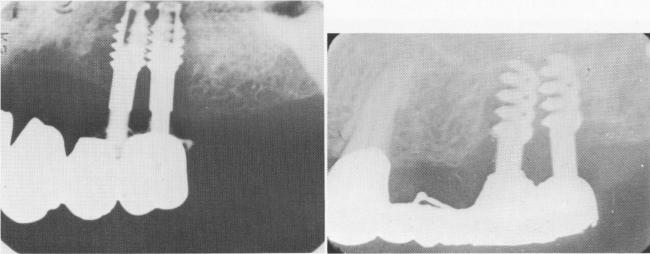

Fig. 14-19. These two radiographs reveal a rapid resorption of bone because of the proximity of the implants. They should be set at least 4 mm. away from one another.